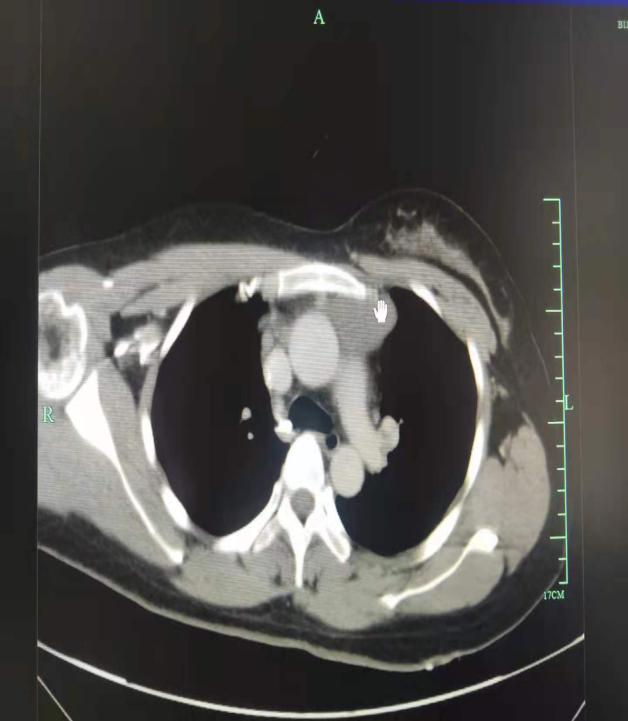

患者张某某,中年女性,1月前患者无意中发现右前颈部有一肿块,无明显疼痛,偶有潮热、盗汗及乏力情况,先后求诊于毕节市多家医院未果。该患者收治于我院外四科,根据患者相关检查,初步判断为纵膈肿瘤,此疾病随着时间延长,肿瘤逐渐增大,将会压迫神经、呼吸系统、食管以及大血管,对身体危害性极大。为此,我院陈刚教授、张月贵医师决定对患者开展我市首例经胸腔镜单操作孔前上纵膈肿瘤微创切除,以切除病灶,同时明确肿瘤性质,手术于8月26日顺利完成,术后效果良好。